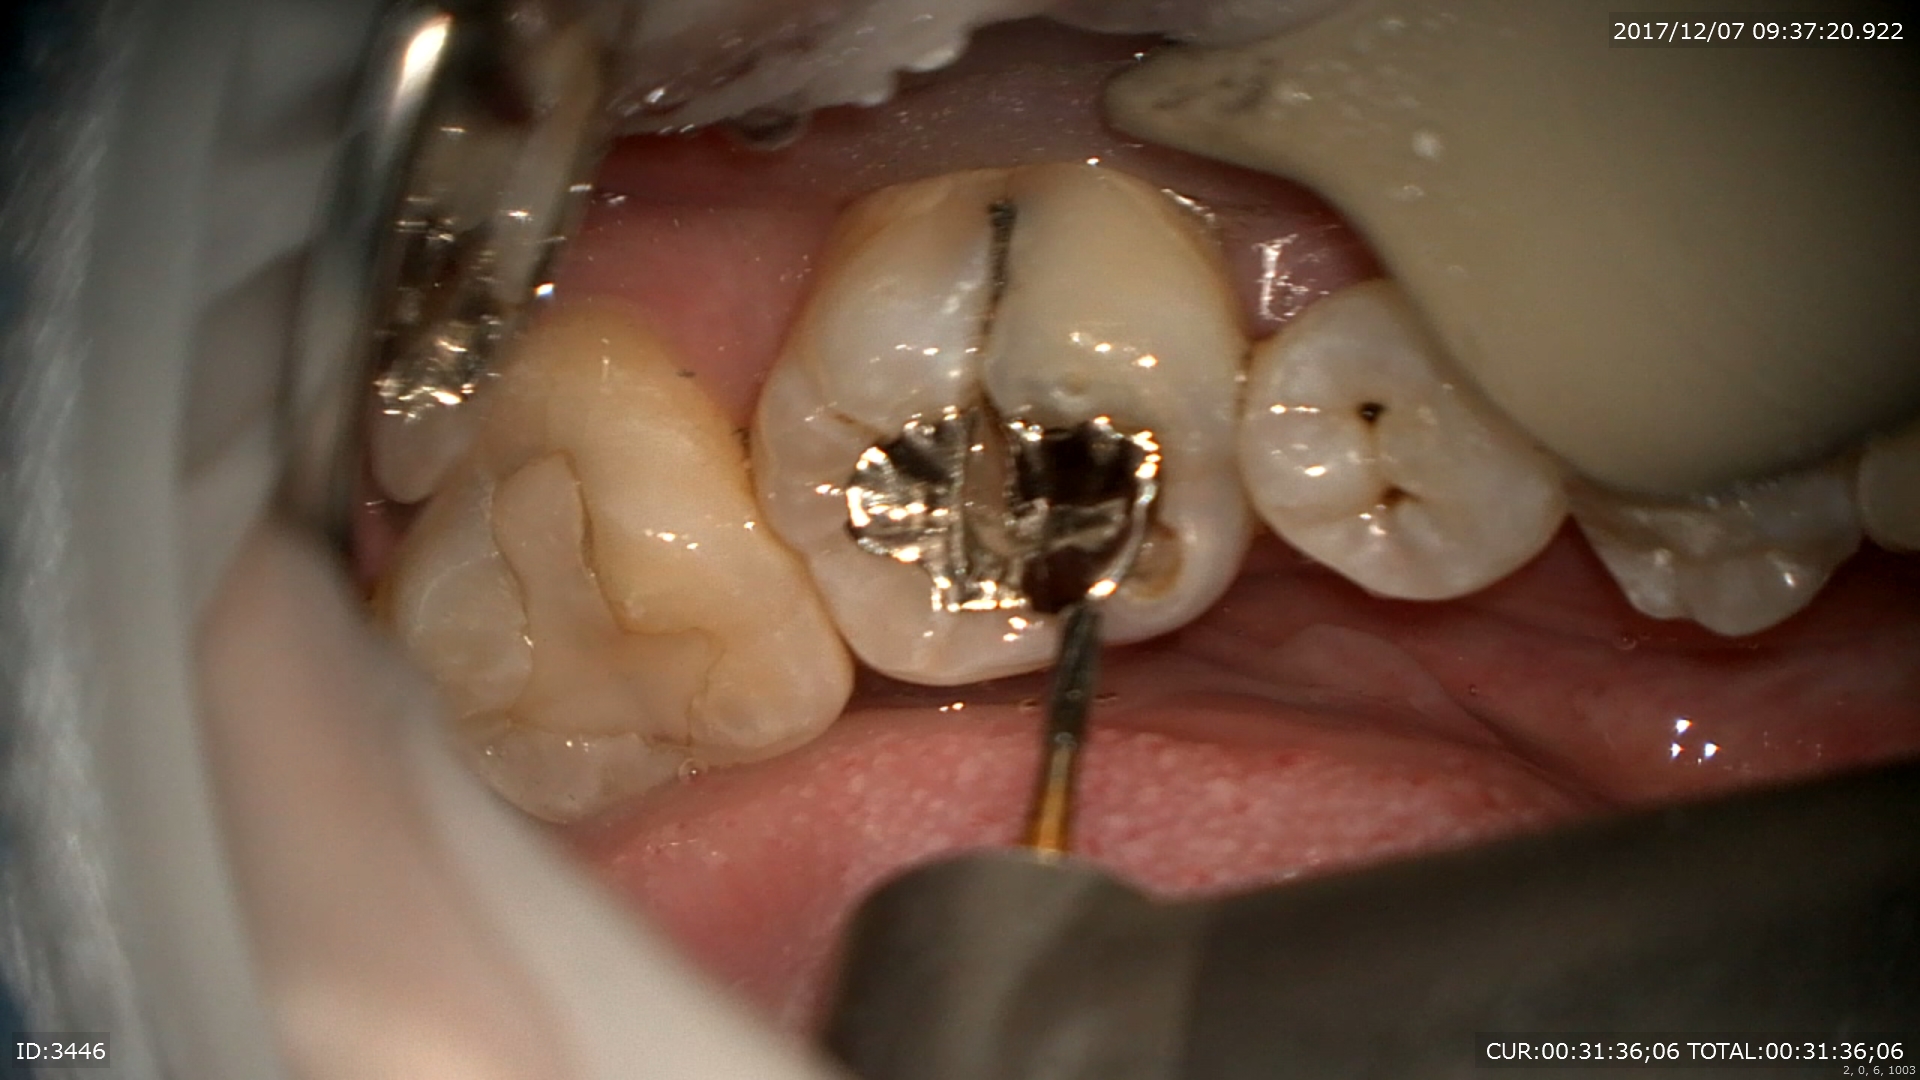

2ケース目:銀歯虫歯。私はこの銀歯治療は行いませんが、この銀歯を行わない理由がここにあります。銀歯が腐食していますね。

中は

こんな感じ